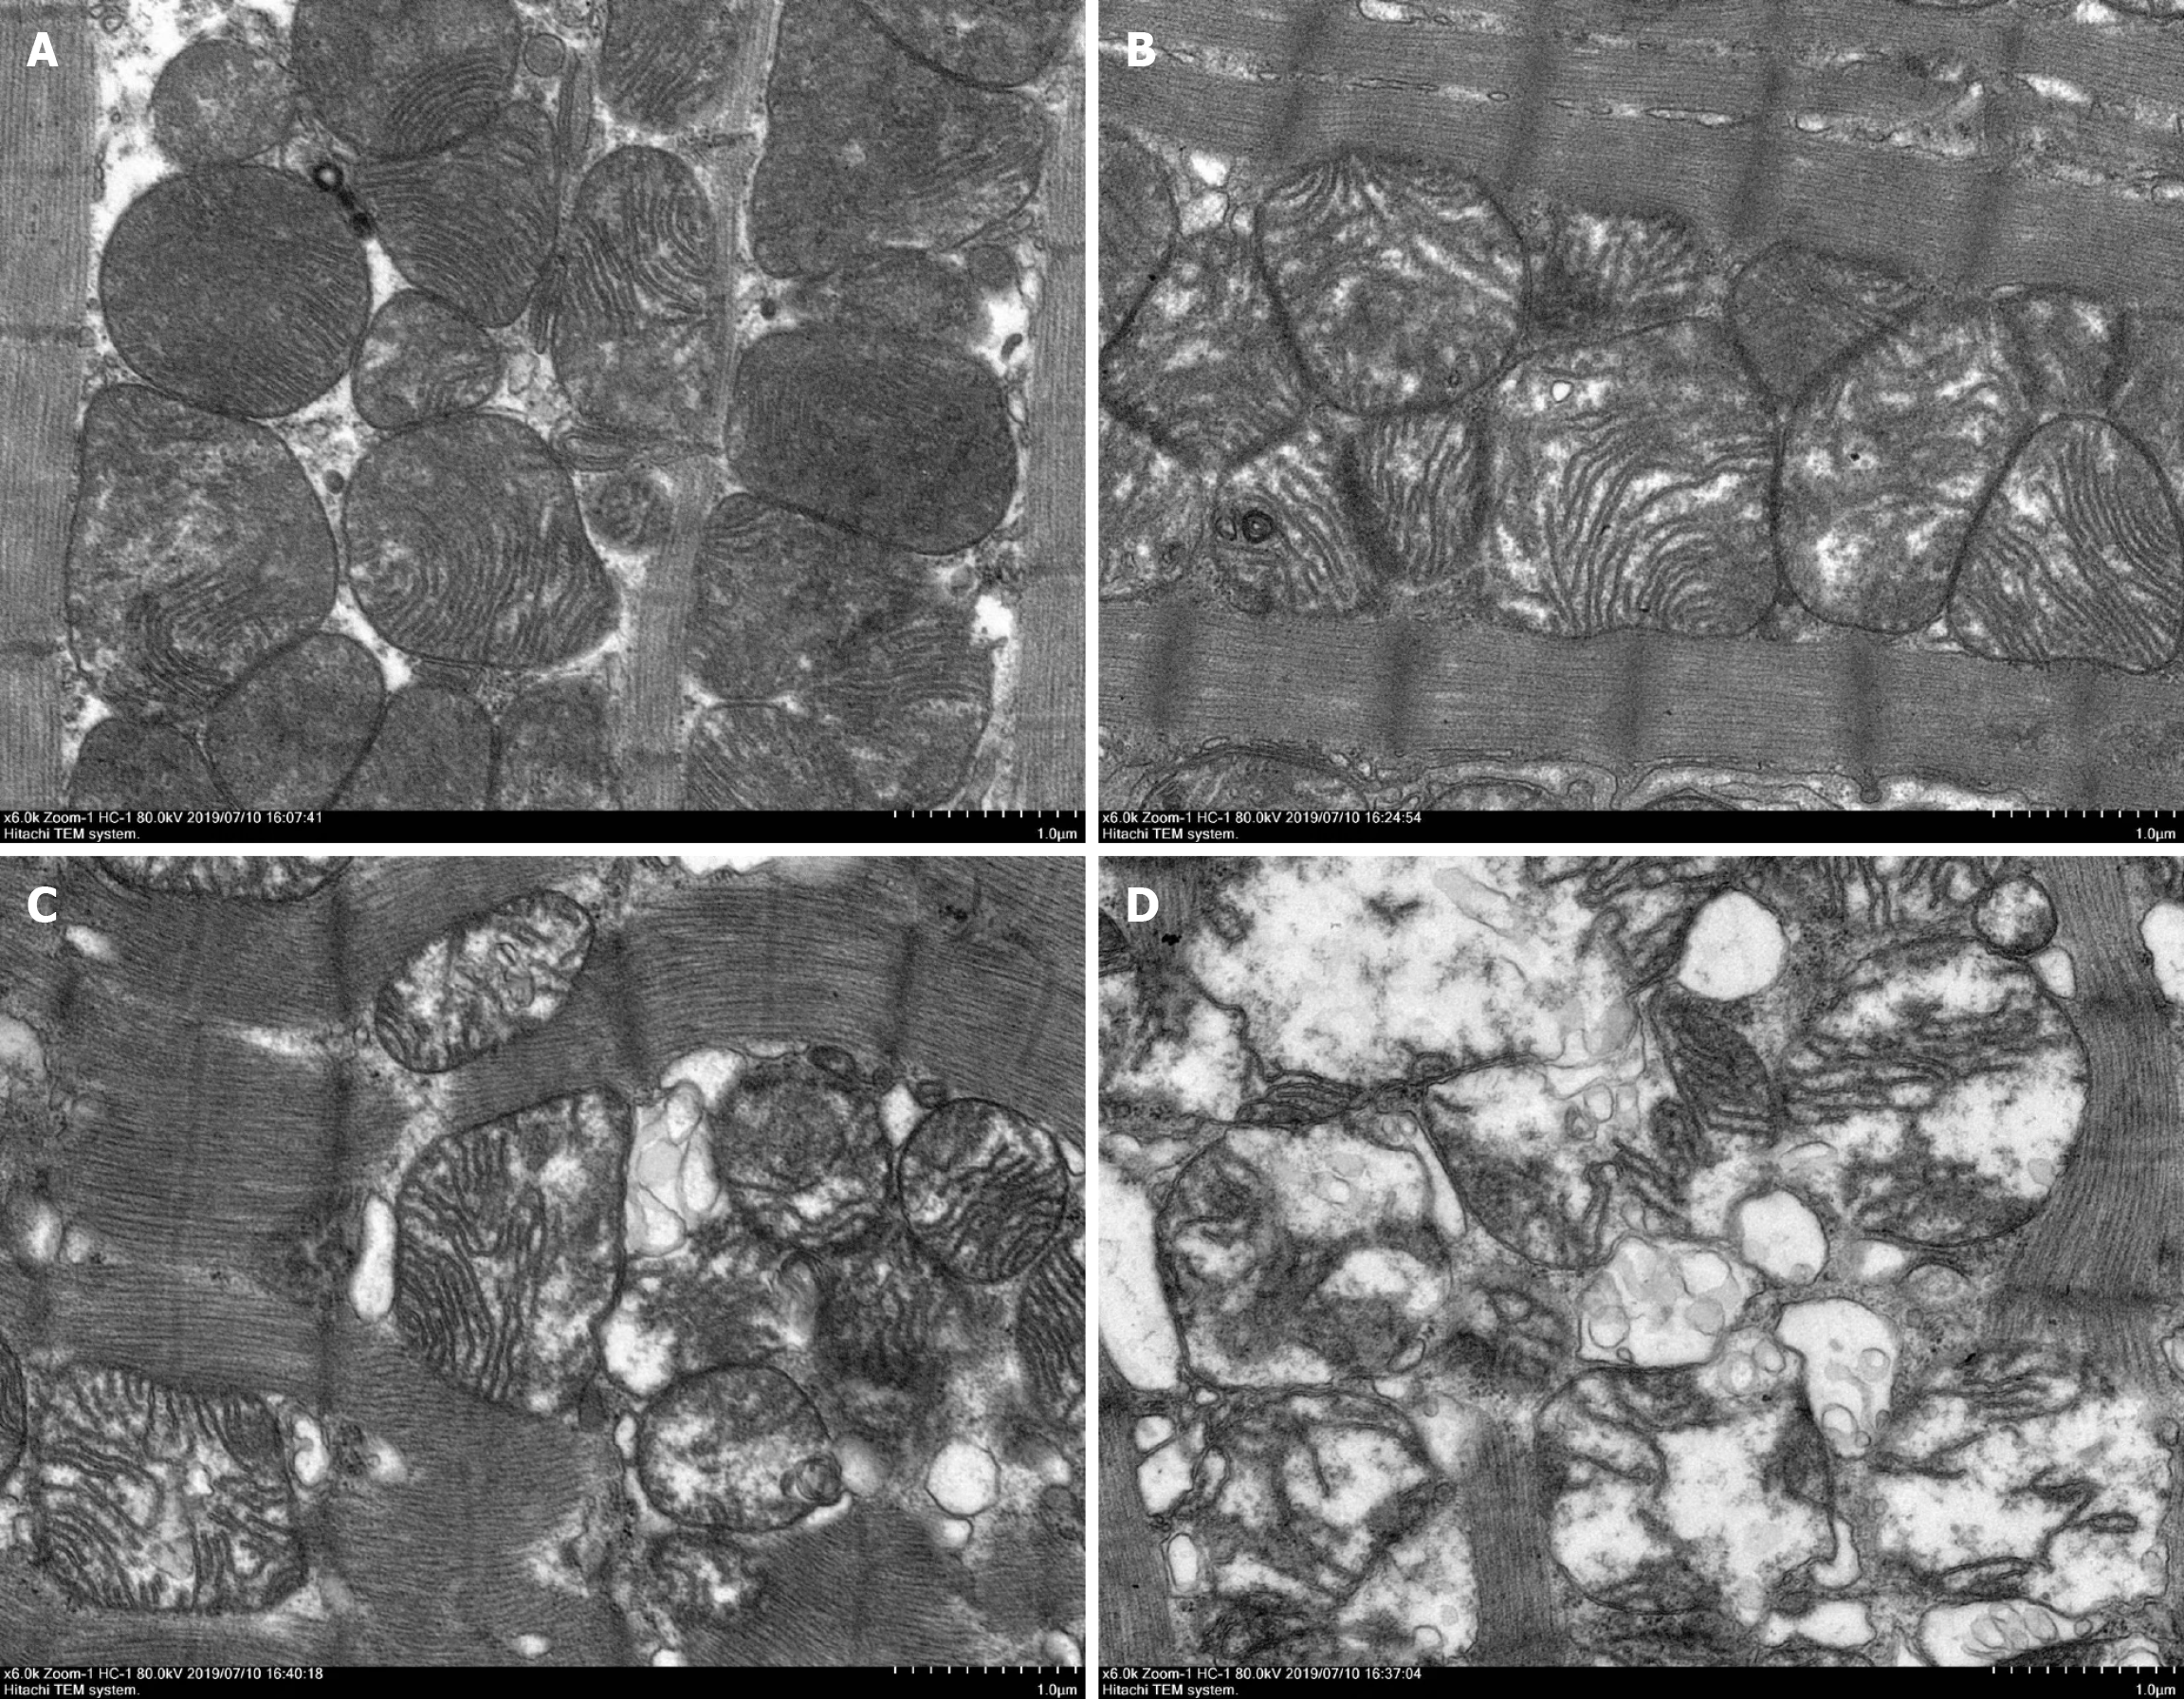

Rat left ventricular tissues were excised and fixed in 4% glutaraldehyde solution in 2%–4.1% osmic acid and 0.1M PBS (pH 7.4) and fixed at 20°C for 2 hours. The tissue samples underwent dehydration, penetration, embedding, slicing and uranium lead double staining. The results were observed by electron microscopy (Tecnai G2 20 Twin).

In the intact sarcomere, it was observed through the use of electron microscopy that the heart tissue of the CON rat exhibited a well-preserved structure, featuring clearly visible mitochondria and myocardial fibers that were neatly arranged in an orderly fashion. Ultrastructural changes in cardiomyocytes were observed in DOX-treated rats. Compared with the CON group, disordered myocardial fibers and vacuolation of mitochondria were found in the DOX groups. Vacuoles in mitochondria disappeared and myocardial fibers were fractured, few and even absent in the 8-week DOX group, compared with the 2-week and 4-week DOX groups (Figure 5).

The current study demonstrates that in rat hearts, the effect of DOX in vivo may be associated with CALU-regulated mitochondrial dynamics and the calcium-Cx43 pathway. Related studies[20,23,24] have shown that DOX can cause pathological damage in the myocardium. In our study, we found that cardiomyocyte fibrosis was more severe in the DOX group than in the CON group, and mitochondrial vacuoles disappeared and myocardial fibers were fractured and fewer in rat hearts treated with DOX, compared with control rat hearts. These findings suggested that the effect of DOX on the heart was related to mitochondria. Mitochondrial dynamics play a crucial role in physiological functions, including the maintenance of mitochondrial DNA stability and critical life processes like energy synthesis and cell aging[19]. Mito